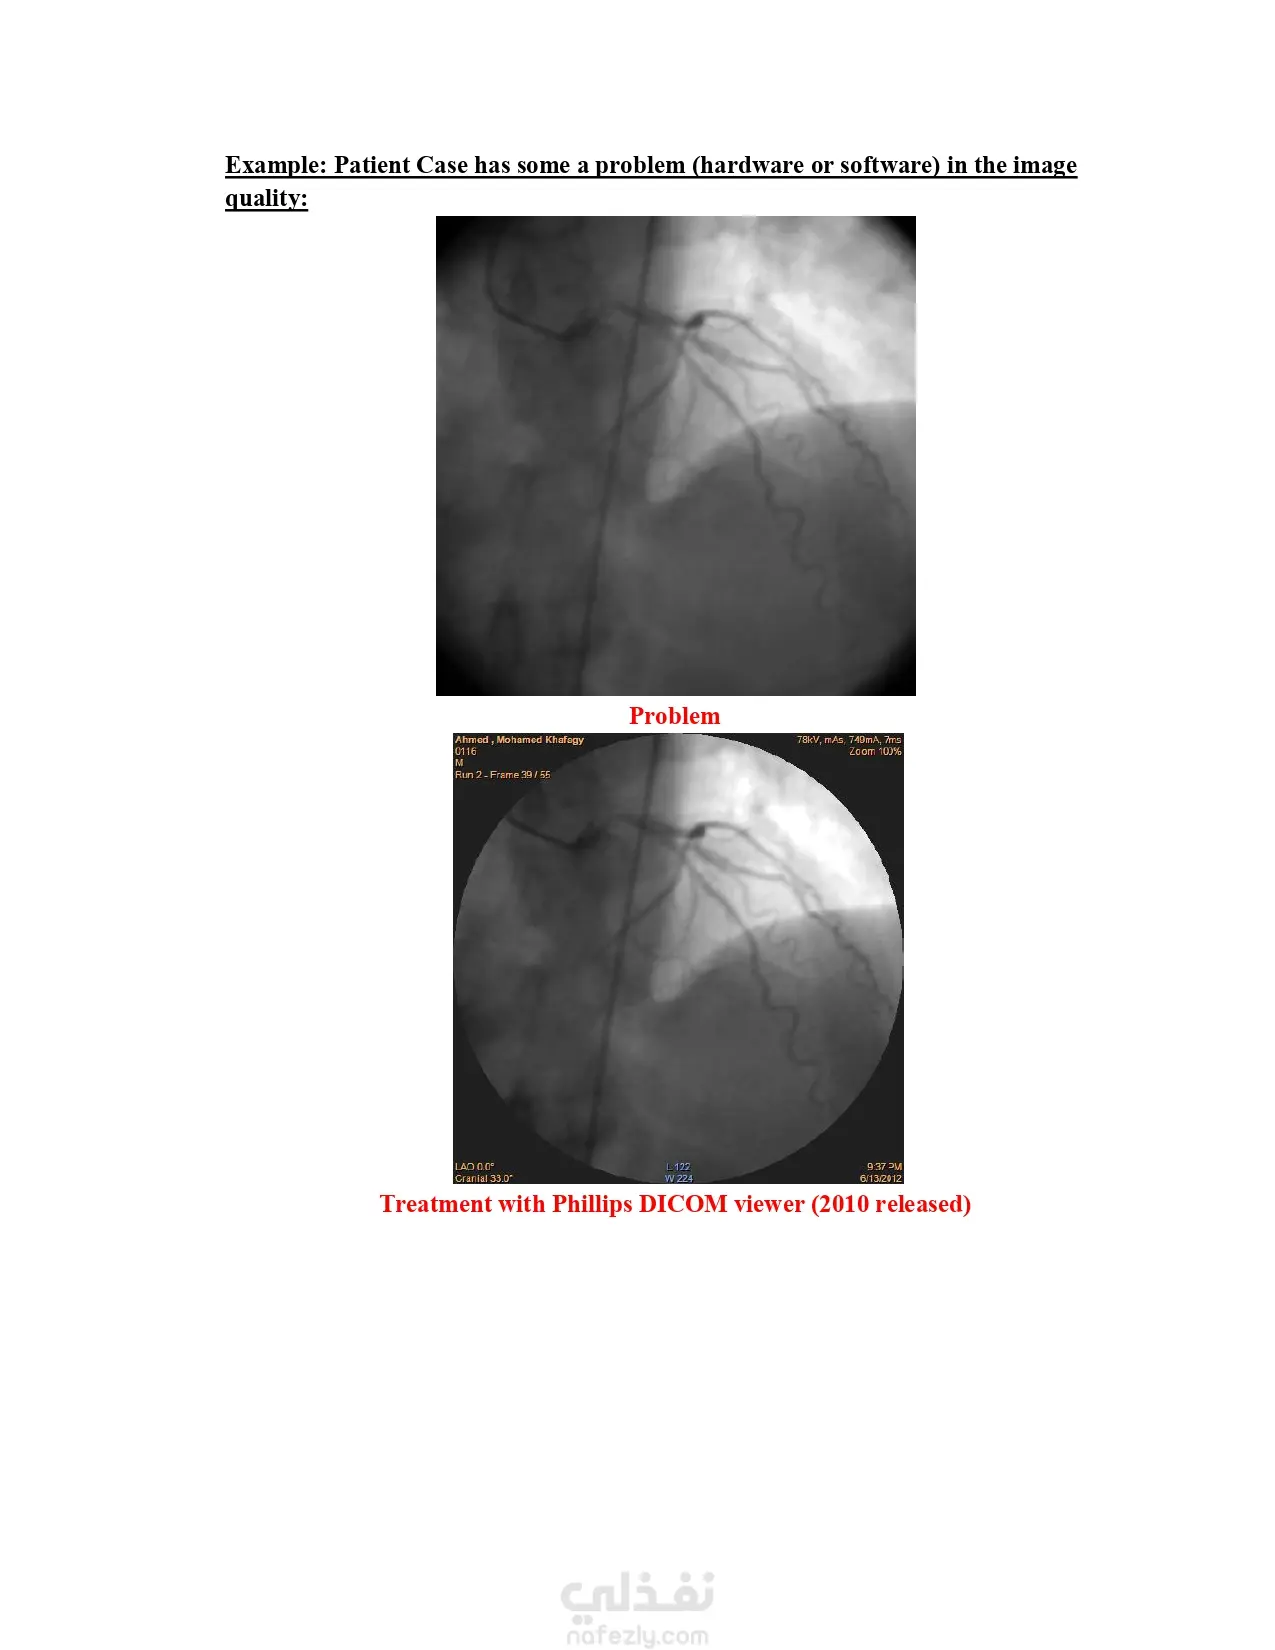

Computer-Aided Diagnosis (CAD) Program – Enhanced CATHLAB image quality using MATLAB for coronary artery diagnosis.